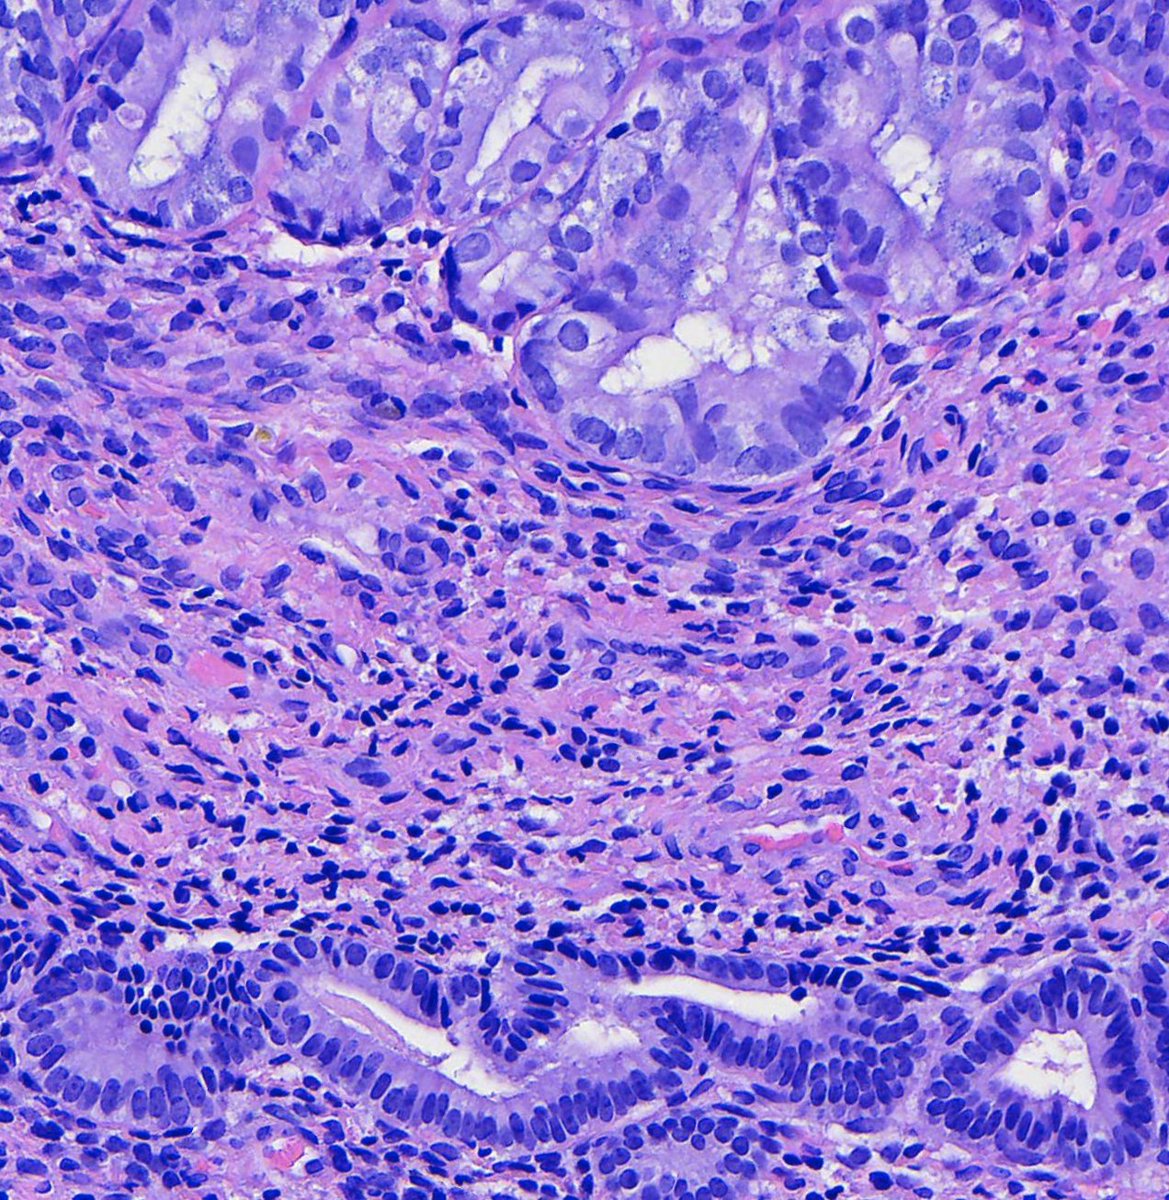

Couldn't be more excited to announce the launch of pathlibrary.com, the virtual slide site I wish had existed during my pathology residency. You can:

- See annotated histologic features